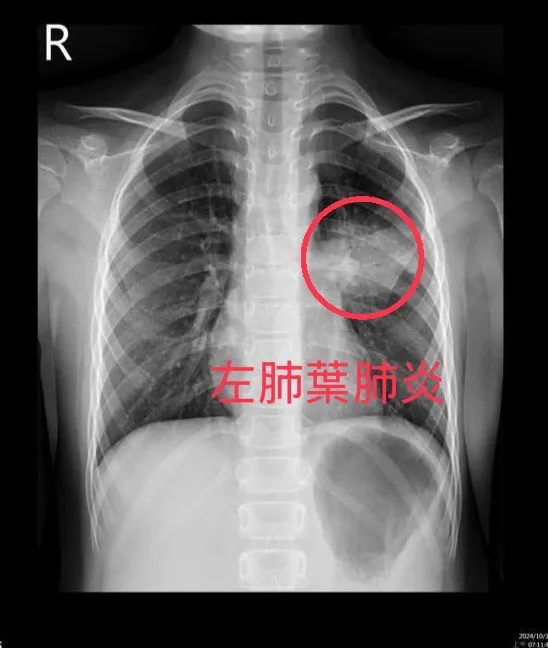

感染黴漿菌的病童有時會出現肺炎症狀,肺部X光白了一片。亞大附醫提供

亞洲大學附屬醫院兒科主治醫師鄭詩橤表示,每到秋冬季節就是流感、黴漿菌、呼吸道融合病毒、腸病毒等呼吸道病菌流行高峰,尤其腸病毒目前還處於流行期,近來卻發現黴漿菌感染比例逐漸攀升,目前住院病童中,就有將近五成檢驗出感染黴漿菌,其中還有病童出現肺炎症狀,「肺部X光白了一片」。